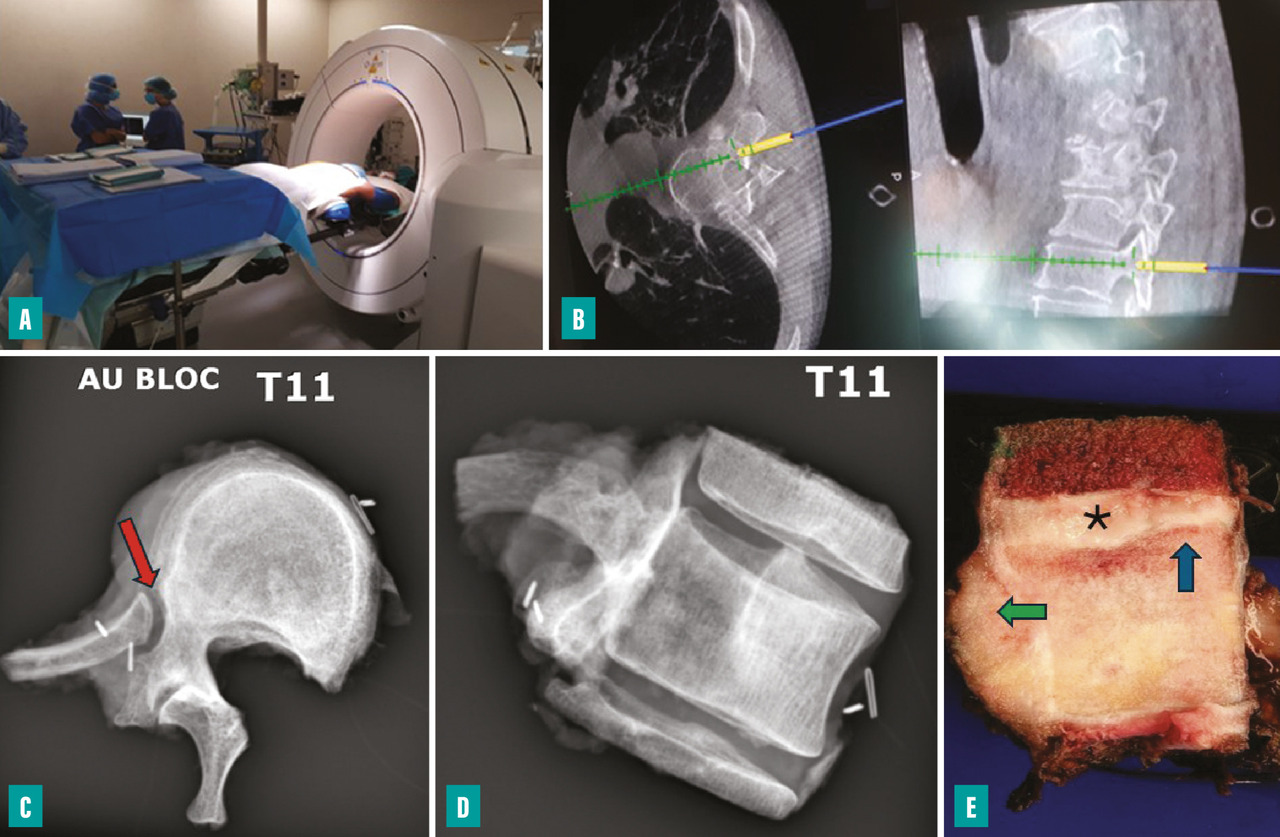

L’utilisation de guides de coupe sur mesure ou d’un système de navigation scanographique peropératoire permet d’augmenter la précision des coupes osseuses et améliore le confort de l’opérateur.2 Un cartilage de croissance actif constitue une barrière anatomique efficace qui permet de diminuer l’épaisseur de la résection et augmente ainsi les possibilités de conservation épiphysaire. Une extension extra-osseuse importante complexifie l’obtention de marges saines.

L’utilisation d’un système de navigation peropératoire (scanner peropératoire ou guides de coupe) permet de contrôler le trajet de l’ostéotomie (fig. 4). La libération de la moelle n’est possible que si au moins un des deux pédicules (voire une lame) est intact. Pour le rachis cervical, l’exposition lors de la libération antérieure est essentiellement limitée par les rapports avec les artères carotides externes et les artères vertébrales. Une interruption du flux artériel est parfois rendue nécessaire afin de limiter le saignement peropératoire (ligature de la carotide externe ou occlusion endovasculaire de la vertébrale).